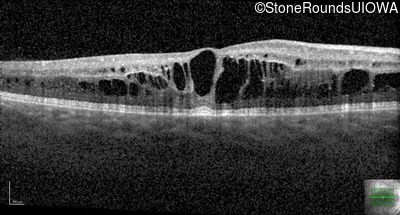

Optical Coherence Tomography - Left - 20/50 -2

Exemplar / OCT Stack

OCT Stack